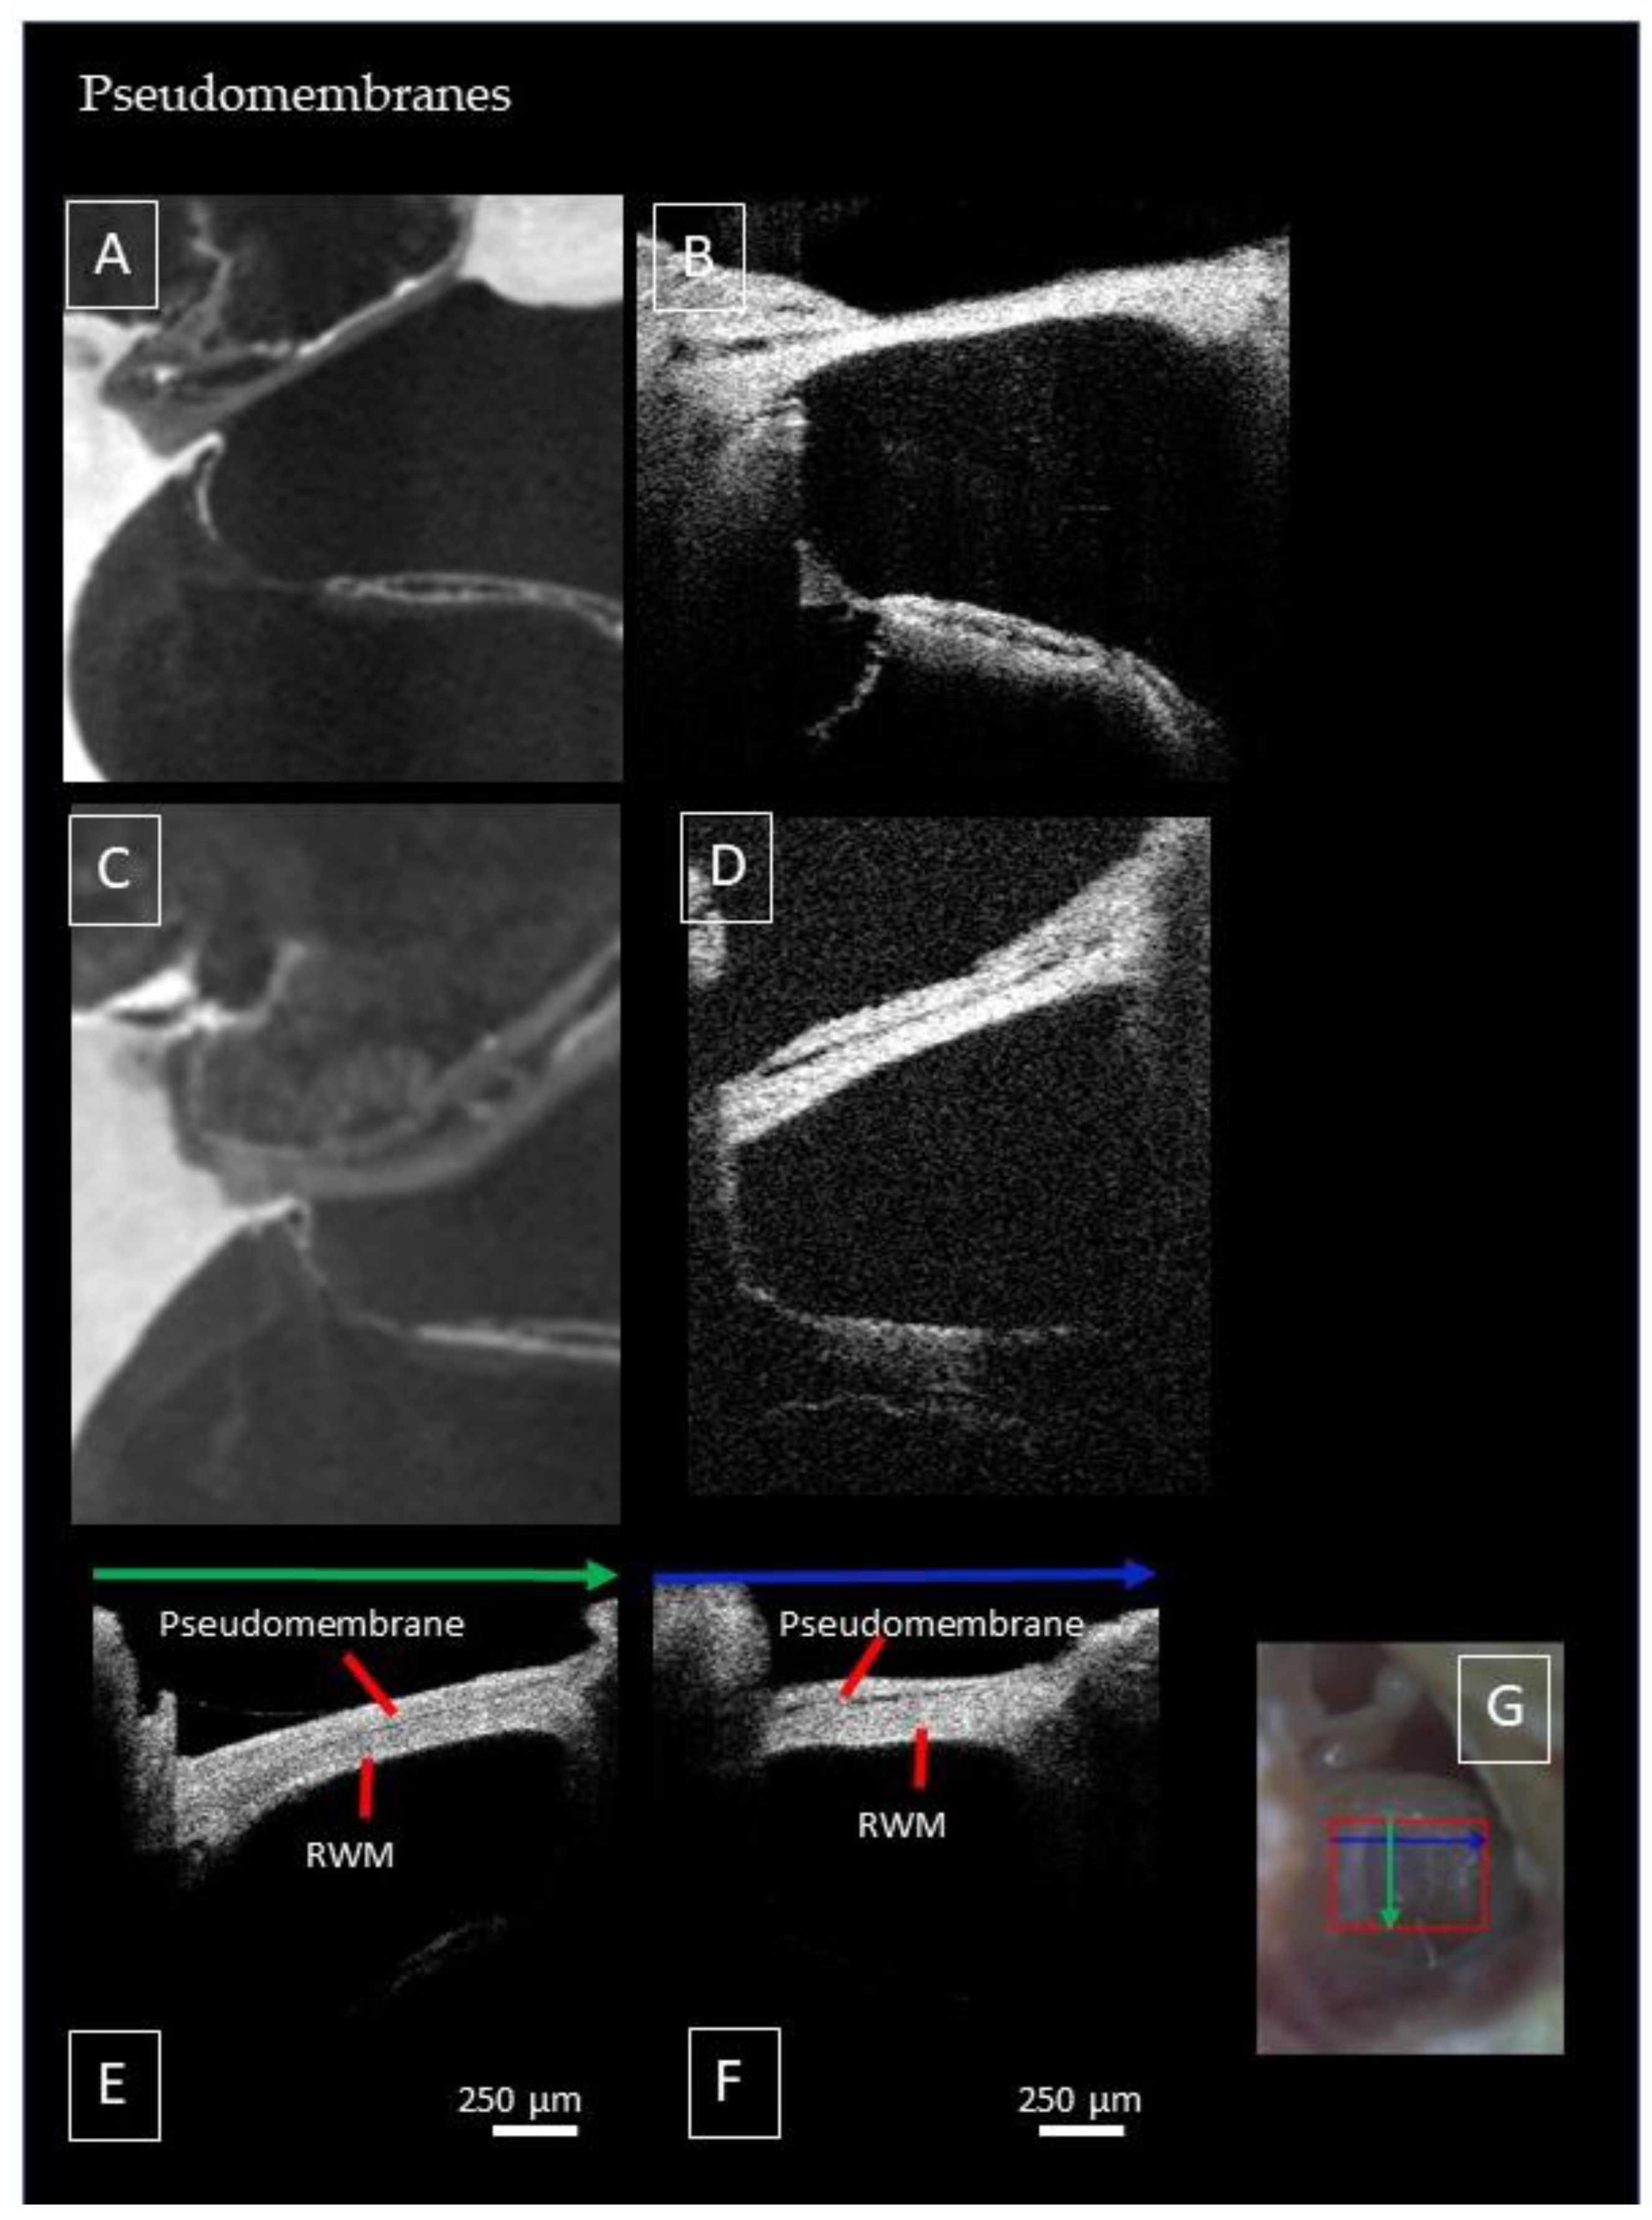

3.4. Deviating Appearance of Intracochlear Structures

3.5. Factors Limiting Imaging through the RWM